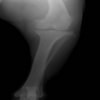

術後側面像

術後正面像

術前に25°であったTPAは、TPLO実施により7°に矯正されました。症例の歩行状態は良好です。